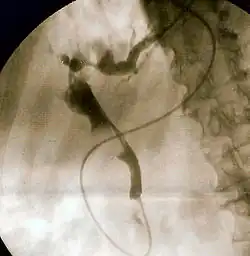

Endoscopic retrograde cholangiopancreatography (ERCP) is a technique that combines the use of endoscopy and fluoroscopy to diagnose and treat certain problems of the biliary or pancreatic ductal systems. It is primarily performed by highly skilled and specialty trained gastroenterologists. Through the endoscope, the physician can see the inside of the stomach and duodenum, and inject a contrast medium into the ducts in the biliary tree and/or pancreas so they can be seen on radiographs.

ERCP is used primarily to diagnose and treat conditions of the bile ducts and main pancreatic duct,[1] including gallstones, inflammatory strictures (scars), leaks (from trauma and surgery), and cancer. ERCP can be performed for diagnostic and therapeutic reasons, although the development of safer and relatively non-invasive investigations such as magnetic resonance cholangiopancreatography (MRCP) and endoscopic ultrasound has meant that ERCP is now rarely performed without therapeutic intent.[2]

The patient is sedated or anaesthetized. Then a flexible camera (endoscope) is inserted through the mouth, down the esophagus, into the stomach, through the pylorus into the duodenum where the ampulla of Vater (the union of the common bile duct and pancreatic duct) exists. The sphincter of Oddi is a muscular valve that controls the opening to the ampulla. The region can be directly visualized with the endoscopic camera while various procedures are performed. A plastic catheter or cannula is inserted through the ampulla, and radiocontrast is injected into the bile ducts and/or pancreatic duct. Fluoroscopy is used to look for blockages, or other lesions such as stones.[8][9]

When needed, the sphincters of the ampulla and bile ducts can be enlarged by a cut (sphincterotomy) with an electrified wire called a sphincterotome for access into either so that gallstones may be removed or other therapy performed.[10]

Other procedures associated with ERCP include the trawling of the common bile duct with a basket or balloon to remove gallstones and the insertion of a plastic stent to assist the drainage of bile.[11] Also, the pancreatic duct can be cannulated and stents be inserted.